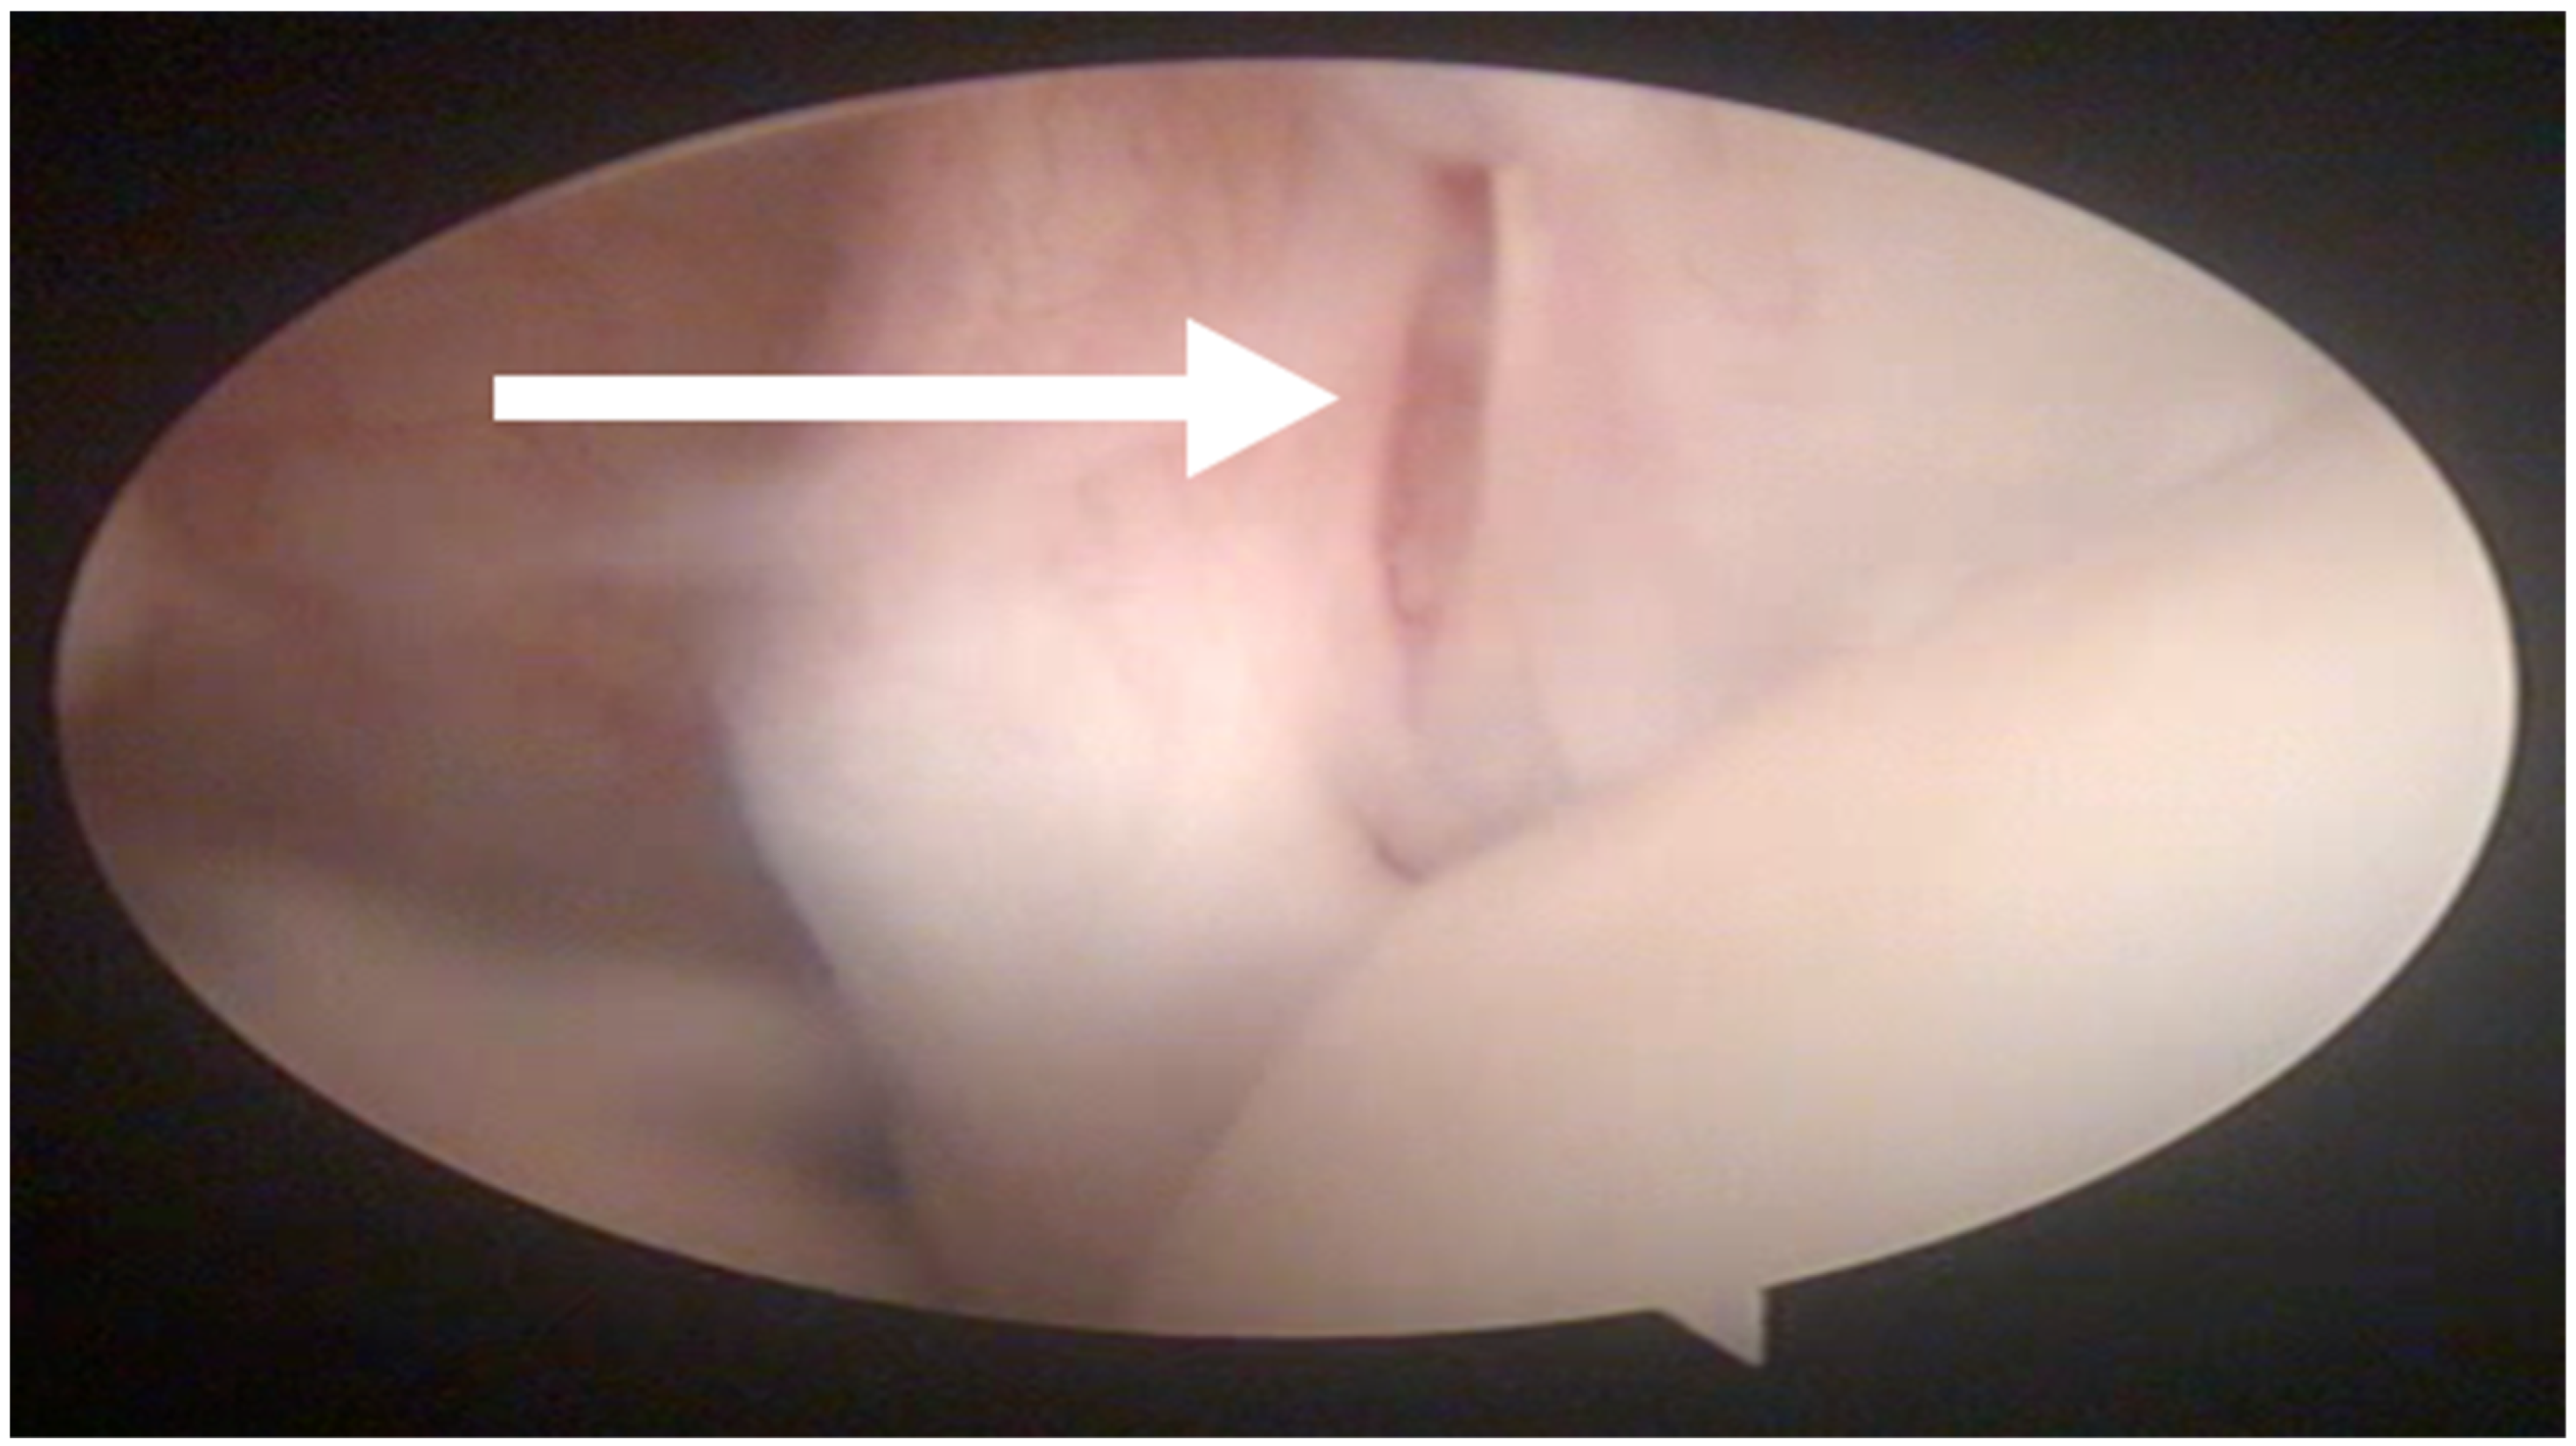

In all the dogs, surgery was performed by the same surgeon only in the shoulder affected by lameness. Intra-articular abnormalities were arthroscopically observed in 13 out of 27 shoulders and consisted of fibrillation of the medial glenohumeral ligament in 3 out of 27 cases, partial rupture of the tendon of the subscapularis muscle in 7 out of 27 cases and laxity of the tendon of the subscapularis muscle in 3 out of 27 cases (Figure 2).

Figure 2. Arthroscopic evaluation of the tendon of the sub-scapularis muscle. A partial rupture is indicated by the white arrow.